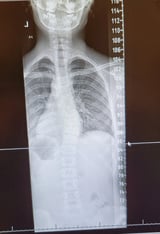

This was my daughter’s plain films:

Her Cobb angle measured 26 degrees and an X-Ray of her hand was taken to determine her Risser sign, which was Risser 2. The Cobb angle is defined as the greatest angle at a particular region of the vertebral column, when measured from the superior endplate of a superior vertebra to the inferior endplate of an inferior vertebra. The angle formed at the intersection of these two lines is the Cobb angle.